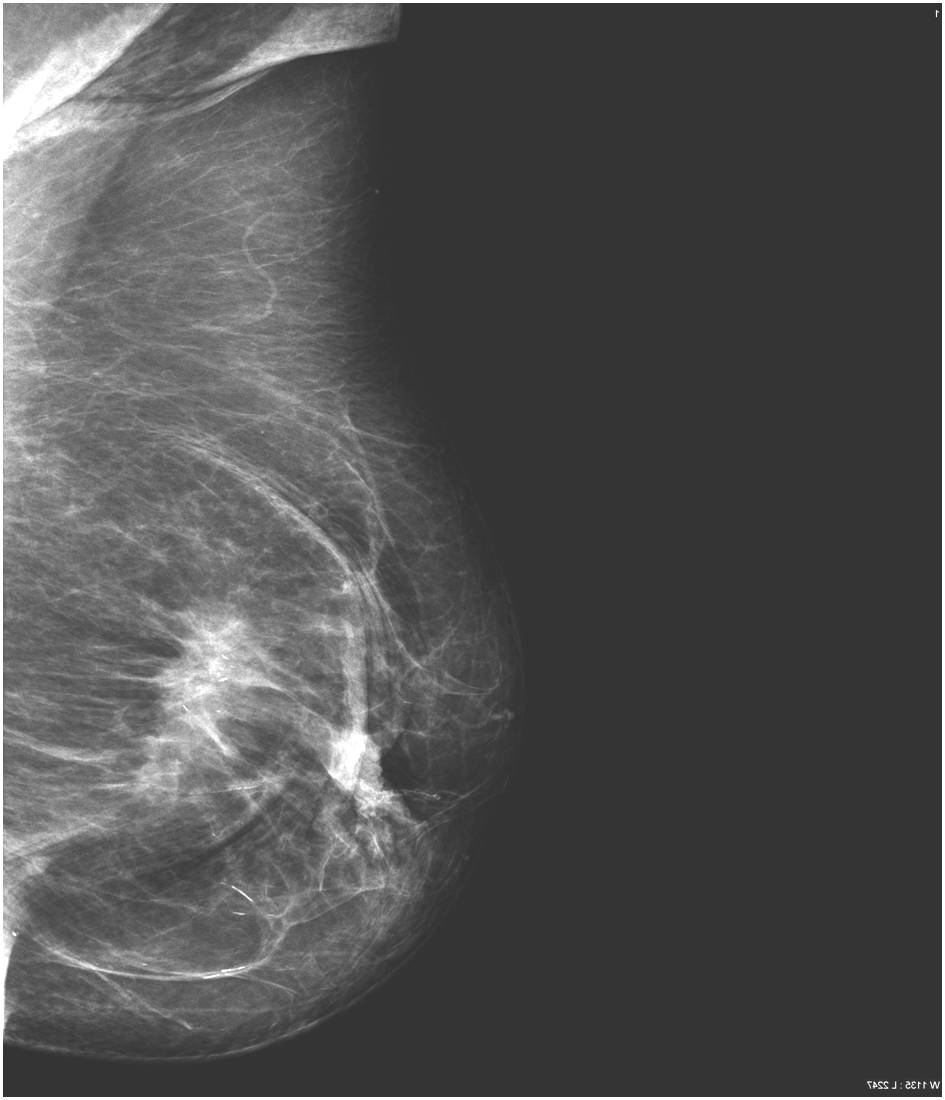

2. Digital mammography has displaced the analogue technic for today almost everywhere: (pictures 1,2,3) phosphorous plate or direct digital methods. For breast imaging the latter is the method of choice. Phases of image production separate. The image is produced on the detectors, but appears on the high resolution monitor and can be stored as a digital data set at various storage mediums (e.g.: CD, hard disk drives).

Image

Picture 1.

Picture 2.

Picture 3.